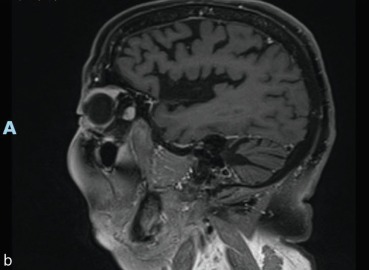

fig. 8-3

a, b. Infiltration en bouée des culs-de-sac dont le cul-de-sac supérieur.